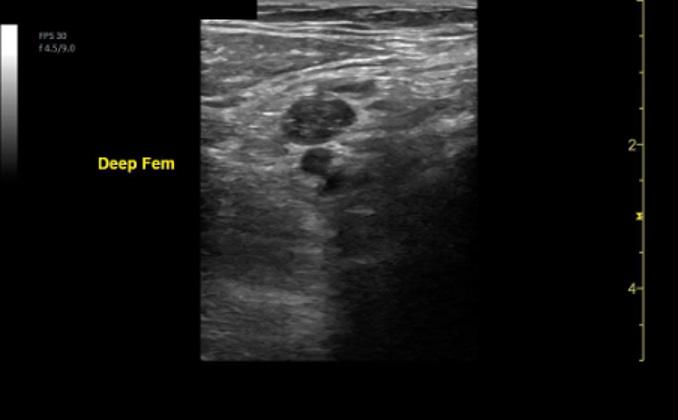

Dr. Artiga’s academic interests include ultrasound, education, and advocacy. Within SAEM RAMS, he has led initiatives such as the Ask-A-Chair educational podcast series, advocacy efforts related to unionization, social media campaigns to promote resident engagement, and the development of board review resources for emergency medicine certification. He has recently taught ultrasound to emergency medicine programs in Latin America.

It was an extremely humbling and eye-opening experience. I went to teach in my father’s country, El Salvador, where I had never visited before. I never truly understood the conditions he lived in beyond his words. All the issues that exist in the U.S. are magnified when you go to countries that don’t have similar resources. Medical decision making is limited by access to resources. It’s not about a lack of capability. I worked with incredibly brilliant doctors who just don’t have access to the same technology or infrastructure we have here. That’s why I believe in supporting ultrasound specifically in these settings. In capable hands, point-ofcare ultrasound can give a clinician life-saving information. Providing this tool and empowering physicians to use it can have a huge impact on individual patients and healthcare systems across the world.

For me, it’s been about chasing my passion and asking, “Who’s on this ride with me?” I’ve always been drawn to ultrasound. Through SAEM’s and the Academy for Emergency Ultrasound’s (AEUS’s) ultrasound didactics and activities, I’ve noticed similar faces showing up. These spaces allow for ideas to connect and develop in ways that don’t happen when you're working alone. You can’t have synergy in isolation. You need people who challenge and inspire you to promote growth. It’s individuals working together, learning from one another, and pushing ideas forward that produce progress.